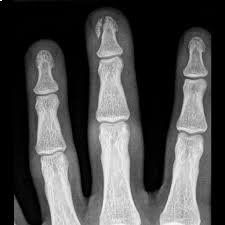

La radiologia convenzionale è l’esame di primo livello per lo studio di molteplici distretti corporei e in particolare dell'apparato respiratorio e scheletrico (cranio, colonna vertebrale, segmenti ossei). Questa metodologia fornisce importanti indicazioni di base su molte patologie, sia traumatiche che degenerative e artrosiche nonché malformative. La radiologia convenzionale si risulta anche di grande efficacia per individuare patologie o problematiche all'apparato urinario e all'addome, da approfondire successivamente con esami diagnostici più accurati e precisi.